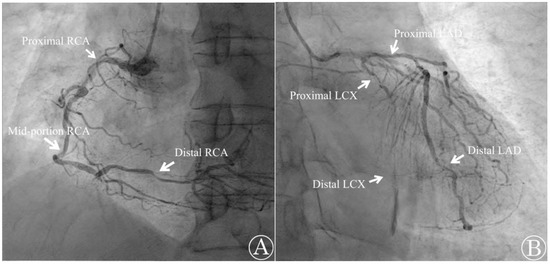

Emergency TTE, coronary angiography (CAG), and computed tomography angiography (CTA) were performed at the cardiology center. The TTE revealed that the patient’s ventricular function was preserved with an LVEF of 68% and did not show any valvular abnormalities. However, the CAG report indicated that the patient had three-vessel CAD with multiple diffuse stenoses. The right coronary artery, left circumflex artery, and left anterior descending artery were found to have stenoses of up to 90%, 100%, and 80%, respectively (Figure 4). The percutaneous coronary intervention was not possible due to the complexity of the case and the presence of three-vessel CAD with stenoses above 70%. The CTA also revealed diffuse atherosclerosis, with multiple atheromas along the thoracoabdominal aorta, and severe (>70%) intramammary artery stenosis. Cardiac biomarker levels that were sampled in the operating room later confirmed elevated cardiac troponin I (cTnI) and lactate dehydrogenase (LDH) with levels measuring 21.5 pg/mL and 225 U/L, respectively. Creatinine kinase-MB (CK-MB) was at 2.82 ng/mL, which was within the normal limit. The patient was diagnosed with type 2 MI and later transferred to the cardiothoracic surgery department to undergo elective CABG surgery a week later. The surgery was uneventful, and the patient was discharged 3 weeks later after recovery.

Figure 4. Emergency coronary angiography shows occlusion in multiple sites. (A) The right coronary artery (RCA) was found to be occluded by 90% at the proximal segment, 70% at the mid-portion, and 80% at the distal segment; (B) the left circumflex artery (LCX) was occluded by 95% at the proximal segment and 100% at the distal segment. The left anterior descending artery (LAD) was occluded 80% at both the proximal and distal portions.